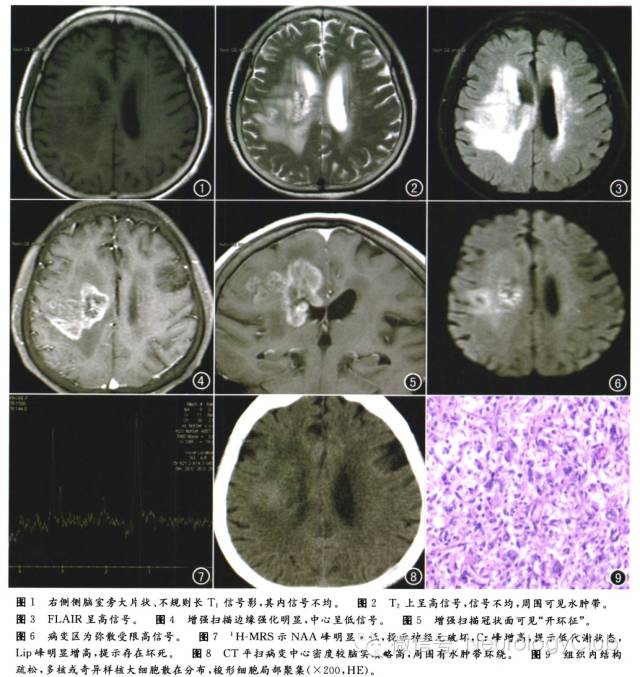

患者,女,78岁,头痛头晕、左侧肢体活动不灵伴言语不清及吞咽困难27d,加重12d。MR表现:右侧侧脑室旁不规则长T1、长T2信号影(图1、2),FLAIR呈高信号,信号欠均匀(图3),大小约4.7cm×3.5cm,边缘欠光整,周围可见水肿带,侧脑室受压变窄;增强扫描环形强化,呈开环状,病灶垂直于侧脑室(图4、5);DWI右侧侧脑室旁可见斑片状弥散受限高信号影(图6);1H-MRS提示:NAA峰明显峰降低,Cr峰增高,Lip峰增高(图7);CT示右侧侧脑室旁不规则稍高密度影,CT值约37HU,周围可见片状水肿带环绕(图8)。手术及病理所见:显微镜下切开皮层,深部可见肿瘤,肿瘤为黄白色,质地中等,血供一般,组织内结构疏松,多核或奇异样核大细胞散在分布,梭形细胞局部聚集。免疫组化结果:GFAP(+),S-100(+),IDHI(-),NeuN(-),Ki-67(约5%+),P53(±),CD68(散在+)。Olig2(+),网状纤维染色(+),NF(+),支持脱髓鞘假瘤(图9)。

脑内脱髓鞘假瘤(demyelination pseudoturnors,DPT)是介于急性播散性脑脊髓炎和多发性硬化之间的一种特殊类型的中枢神经系统脱髓鞘性疾病,临床较为少见,发病机制目前尚不完全明确,部分学者认为与病毒感染或注射疫苗有关。本病可发生于各个年龄段,主要好发于中青年,常有头痛、反应迟钝、记忆力下降、肢体麻木及瘫痪、病理征阳性等症状和体征。病理学上髓鞘破坏区见单核细胞和泡沫状巨噬细胞浸润是其特征性表现,常伴有反应性肥胖型星型细胞增生,病变区虽有髓鞘破坏,但轴索相对保存完整。影像学检查常因表现为实性肿瘤样占位性病变,而被误诊为肿瘤。CT平扫表现为脑内单发或多发肿块样病变,呈圆形或不规则形,病灶周围可见轻至中度水肿,占位效应相对较轻,可伴出血、坏死及囊变。增强扫描常为环形强化,少数不强化。MRI平扫多表现为单发或多发的圆形、类圆形肿块样结构,T1WI呈均匀低信号,T2WI呈均匀高信号,病灶周围多有水肿及占位效应。增强扫描病灶可呈现环形或半环形强化、斑片状强化、结节状强化等,其中“开环征”(非闭合性的环形强化)与“垂直征”(类似于多发性硬化的直角脱髓鞘征)具有一定的特异性。1H-MRS显示病变区NAA峰明显降低,Cho峰升高不显著,偶可出现明显升高的Glx峰。

脑内脱髓鞘假瘤好发于中青年人。常规影像学检查,脱髓鞘假瘤有一定的影像学特点,病灶常在白质区,呈实性或囊性,常呈圆形或不规则形,病灶占位效应相对较轻(占位效应与病灶大小不匹配),病灶强化方式多样,可呈点片样、团块样及环形,出现非闭合性的环形强化,即“开环征”是脱髓鞘假瘤特征性的征象,环口常开向内侧(指向侧脑室)。但有时脱髓鞘假瘤常规影像学检查缺乏特征性改变,容易被误诊为肿瘤性病变或脓肿,这时,需要借助一些新的检查技术,其中,最有价值的是磁共振灌注检查,脱髓鞘假瘤强化虽然较明显,但由于没有肿瘤新生血管,所以常呈等或低灌注,而肿瘤性病变,如胶质母细胞瘤等常呈明显高灌注。磁敏感加权成像(SWI)检查病灶内常可见到小静脉影,向侧脑室旁引流,是脱髓鞘病变的较特异性改变,在肿瘤性病变中是绝对看不到的。MRS检查对脱髓鞘假瘤诊断也有帮助,用短TE1H-MRS检查中,脱髓鞘假瘤在2.1-2.5ppm区可见谷氨酸复合物(Glx)峰,而肿瘤性病变无Glx峰,但Glx峰通常较小,不容易观察。DWI检查脱髓鞘假瘤常轻度弥散受限。